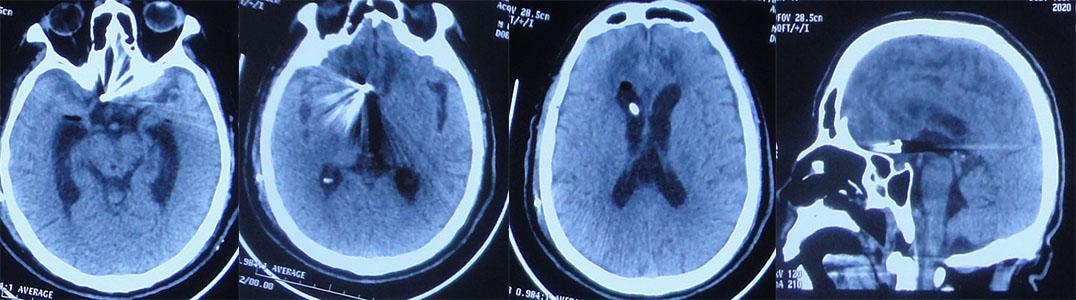

住院次日即2020年10月17日3点行全脑血管造影术示前交通动脉瘤(片子遗失);但当天晚上22时左侧瞳孔散大到边缘,急诊复查脑CT示动脉瘤破裂二次出血( 图-2 )。

图-2: 2020年10月17日头部CT动脉瘤破裂二次出血